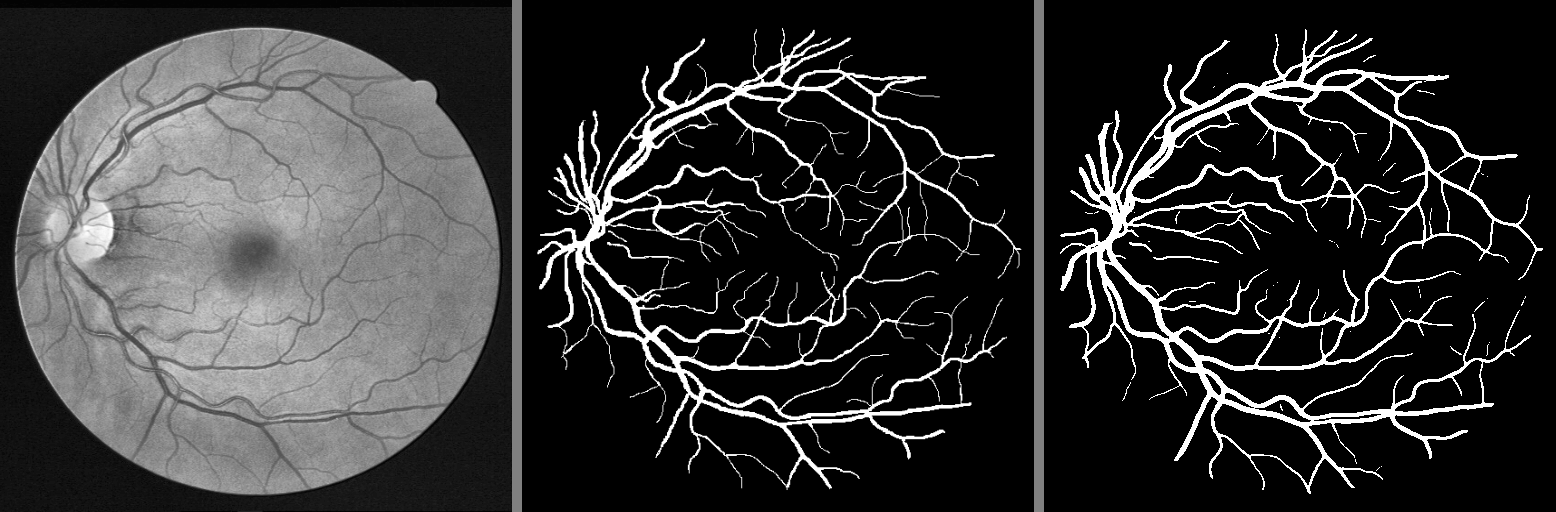

Calculating the mean image and mask provides insights into the average characteristics of the dataset. The mean image (Fig. 2a) reveals the general brightness and common features across all retinal images, while the mean mask (Fig. 2b) shows the typical distribution of vessel locations and their density.

The mean image retains the circular structure of the retina with a high-intensity region corresponding to the optic disc, and a dark, low intensity region corresponding to the fovea. The mean mask, on the other hand, accentuates the primary vessel pathways, emphasizing areas of higher vessel density typically observed in retinal images.

The figure also demonstrates a good property - each person’s retinal vascular tree is unique, which could inspire further research on the use of vessel extraction for biometric identification.